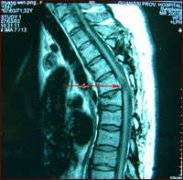

•   【检查】脊髓损伤要做哪些检查?

导读: 脊髓损伤要做哪些检查?脊髓损伤是指由于直接或者间接原因导致患者脊柱发生病变,从而影响患者行为能力的一种神经科疾病,如果不及时进行治疗可能会导致患者瘫痪。清楚脊髓损伤…